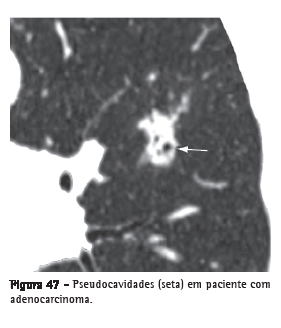

Pseudocavidade

Representa uma área arredondada ou oval de baixo coeficiente de atenuação em nódulos ou massas pulmonares ou em uma área de consolidação secundária a: 1) presença de uma porção de parênquima pulmonar preservado; 2) presença de brônquios dilatados ou mesmo de calibre normal; ou 3) uma área de enfisema no interior da lesão (Figura 47). Estas pseudocavidades geralmente medem menos de 1 cm de diâmetro. Podem ser identificadas em pacientes com adenocarcinoma, carcinoma bronquioloalveolar e pneumonia.(7,72)